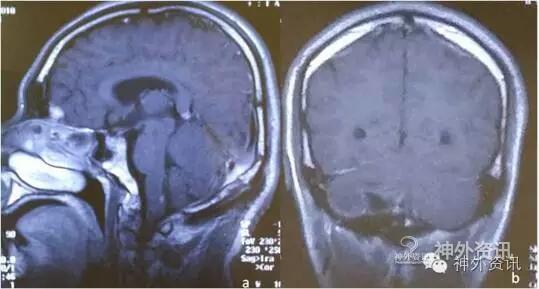

术后症状好转,患者恢复工作。复查MRI未见肿瘤残余(图2)。1月余前再次出现头痛,呈持续性胀痛,当地医院MRI提示:右小脑肿瘤,复发可能。

图2. 术后MRI显示未见肿瘤残留。